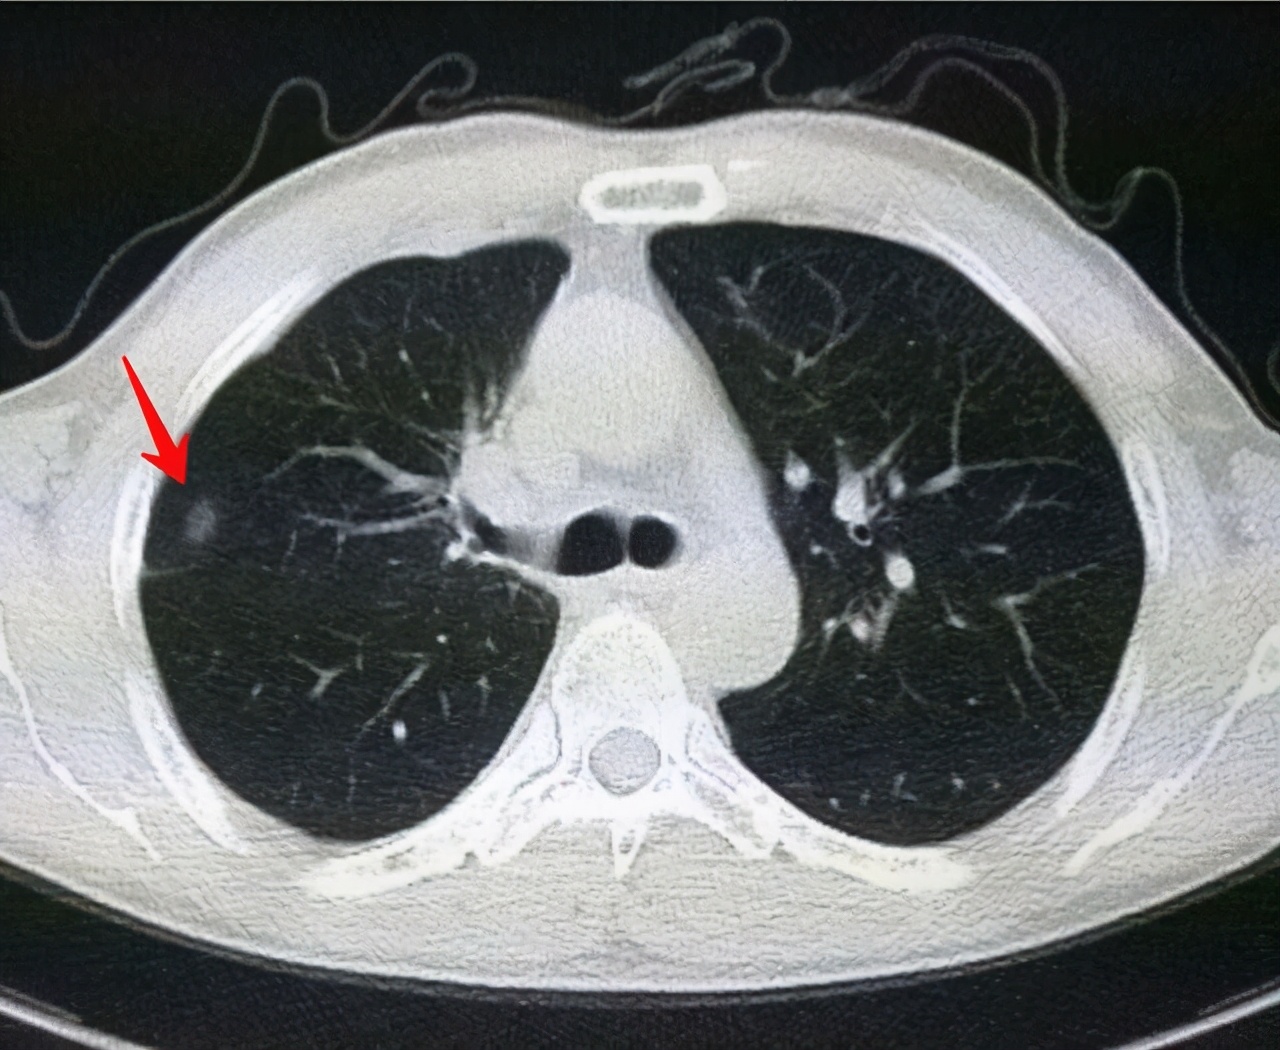

磨玻璃结节

直径在5-10mm的磨玻璃结节,暂时不用手术,3个月复查1次。

结节可以通过药物进行治疗,如果是炎性结节一般可以缩小甚至消失的。如果出现结节长大,或从磨玻璃样的结节逐渐长成实性结节,不用犹豫了,切除吧。毕竟如果癌变了就麻烦了。